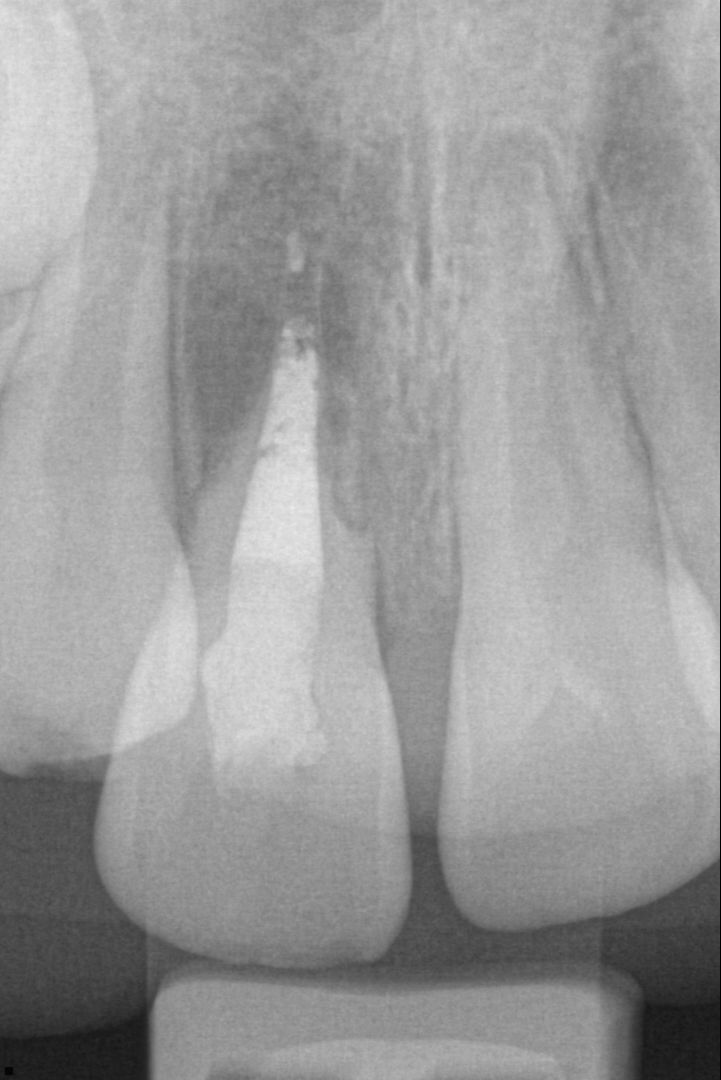

Avulsion immature root